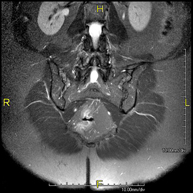

Prova diagnòstica no invasiva que consisteix en l'obtenció d'imatges d'alta definició anatòmica de la pelvis mitjançant l'ús d'un camp electromagnètic i ones de ràdio (amb un emissor i un receptor). No utilitza radiació ionitzant. Es realitza per a l'estudi de patologies d'úter, d'ovari, de trompes i de vagina, ja siguin d'origen tumoral, inflamatori o vascular. També permet valorar les estructures adjacents localitzades a la pelvis i la identificació de les seves alteracions. De vegades és necessari l'ús de contrast intravenós (Gadolini) per caracteritzar les lesions. - RM Pelvis masculina

Prova diagnòstica no invasiva que consisteix en l'obtenció d'imatges d'alta definició anatòmica de la pelvis masculina mitjançant l'ús d'un camp electromagnètic i ones de ràdio (amb un emissor i un receptor). No utilitza radiació ionitzant. No requereix preparació prèvia. En algunes ocasions necessita l'ús de contrast paramagnètic (Gadolini) per caracteritzar les lesions. Aquesta prova permet valorar òrgans com la bufeta urinària, la unió entre els urèters i la bufeta, la pròstata, les vesícules seminals, la uretra i els ossos de la pelvis, entre d'altres. - RM de Fetge